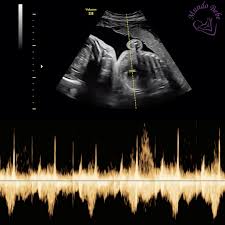

Como Interpretar Los Percentiles Del Bebe Por Ecografia Ecografia 5d Madrid Mundobebe5d